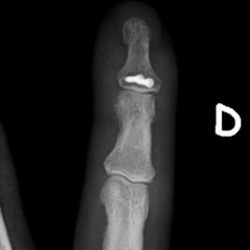

Röntgenbilder